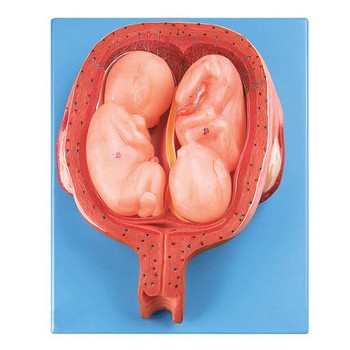

GD/A42005/8五個月雙胞胎模型產品介紹:1、尺寸:自然大,高20.5cm,寬15.5cm,厚8.5cm,共有14個部位指示標志。2、材質:進口PVC材料、進口油漆、電腦配色、高級彩繪有關GD/...